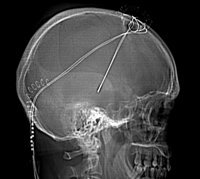

Éstas son la cirugía de implante de estimulación subtalámica bilateral, y las infusiones intraduodenal de 'Duodopa' y subcutánea de apomorfina; que representan todas ellas un coste "superior a los 50.000 euros", asegura el presidente de la Fundación Inbiomed, el doctor Gurutz Linazaroso. Como ejemplo, expone que la primera sólo se aplica "en una veintena de hospitales" del territorio nacional.